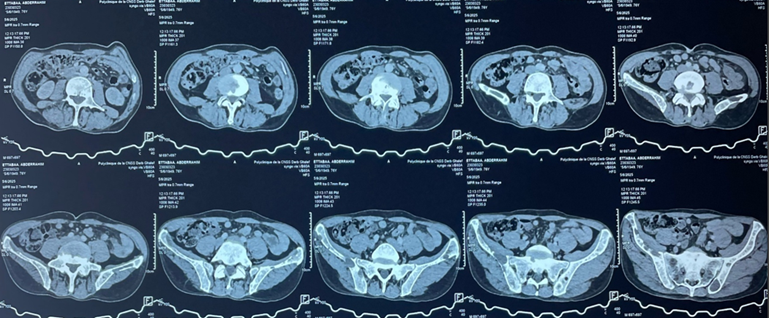

Additionally, multiple costal and vertebral osteolytic lesions were noted (Figure

2). Abdominopelvic CT revealed multiple osteolytic lesions involving the

Figure

2: Axial abdominopelvic CT scan showing osteolytic bone lesions involving

the spine and the pelvis